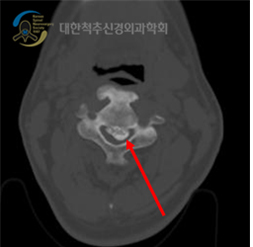

전산화 단층 촬영

척추 관절과 관절 사이의 분리, 척추뼈의 전위된 정도, 척추뼈, 관절, 인대의 비대로 신경이 눌리는 정도를 알 수 있습니다.

후종인대 골화증 검사에서 가장 중요한 검사입니다. 전산화 단층촬영은 골화된 종괴의 모양과 크기, 척추관 협착과 척수 압박 정도를 정확히 알 수 있습니다.